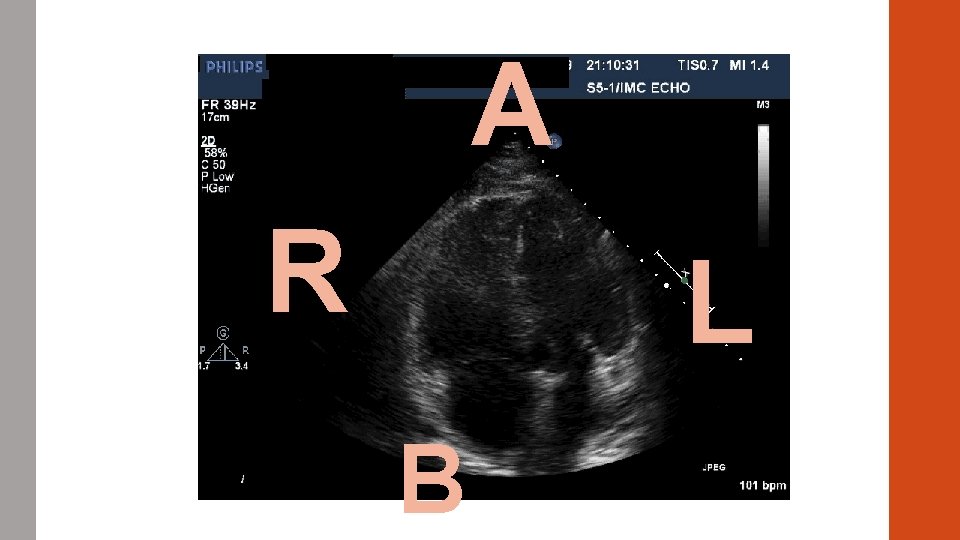

#5 CASE STUDY A 31 year old smoker presents to the ED with acute onset shortness of breath. Symptoms began ~2 hours prior to arrival. Syncopal event en route. She also endorses chest pain. T 98. 0 HR 125 BP 90/55 Sp. O 2 85% on 6 L NC.

A R L B

ABG 7. 56/20/56/24 p. H/CO 2/HCO 3

Diagnosis? Massive PE!